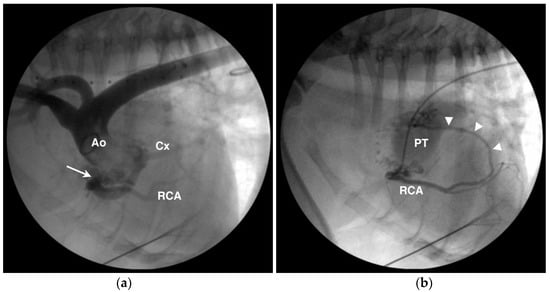

4.2. Anomalous Origin from the Pulmonary Trunk

- Turk, M.A.; Turk, J.R.; Hopkins, M.G.; Wagner, J.A. Unexpected death in an adult dog with anomalous origin of the left coronary artery from the pulmonary trunk. Cornell Vet. 1984, 74, 344–348. [Google Scholar] [PubMed]

- Pelosi, A.; Côté, E.; Eyster, G.E. Congenital coronary-pulmonary arterial shunt in a German shepherd dog: Diagnosis and surgical correction. J. Vet. Cardiol. 2011, 13, 153–158. [Google Scholar] [CrossRef] [PubMed]